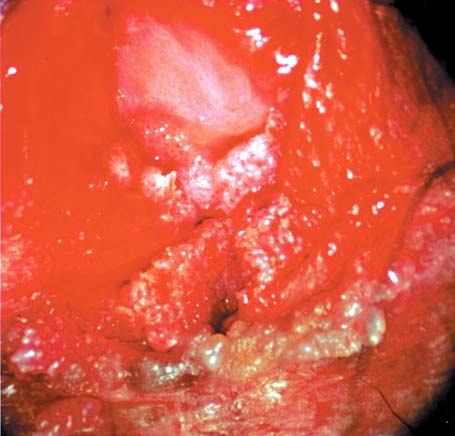

図2.女性外陰部のコンジローム

(帝京大学医学部付属溝口病院産婦人科:川名尚教授提供)

一般に自覚症状に乏しいが、外陰部腫瘤の触知、違和感、帯下の増量、掻痒感、疼痛が初発症状となることが多い。表面が刺々しく角化した隆起性病変が特徴(図2)で、淡紅色~褐色の乳頭状、鶏冠状、あるいはカリフラワー状と表現される。好発部位は、男性では陰茎の亀頭部、冠状溝、包皮内外板、陰嚢で、女性では膣、膣前庭、大小陰唇、子宮口、また男女とも、肛門及び周辺部、尿道口である。子宮頸部、膣に発症した場合は、外陰の病変同様の疣状を呈することもあるが、flat condylomaと呼ばれる扁平な病変を形成することが多い。20~30%は3カ月以内に自然消退する。